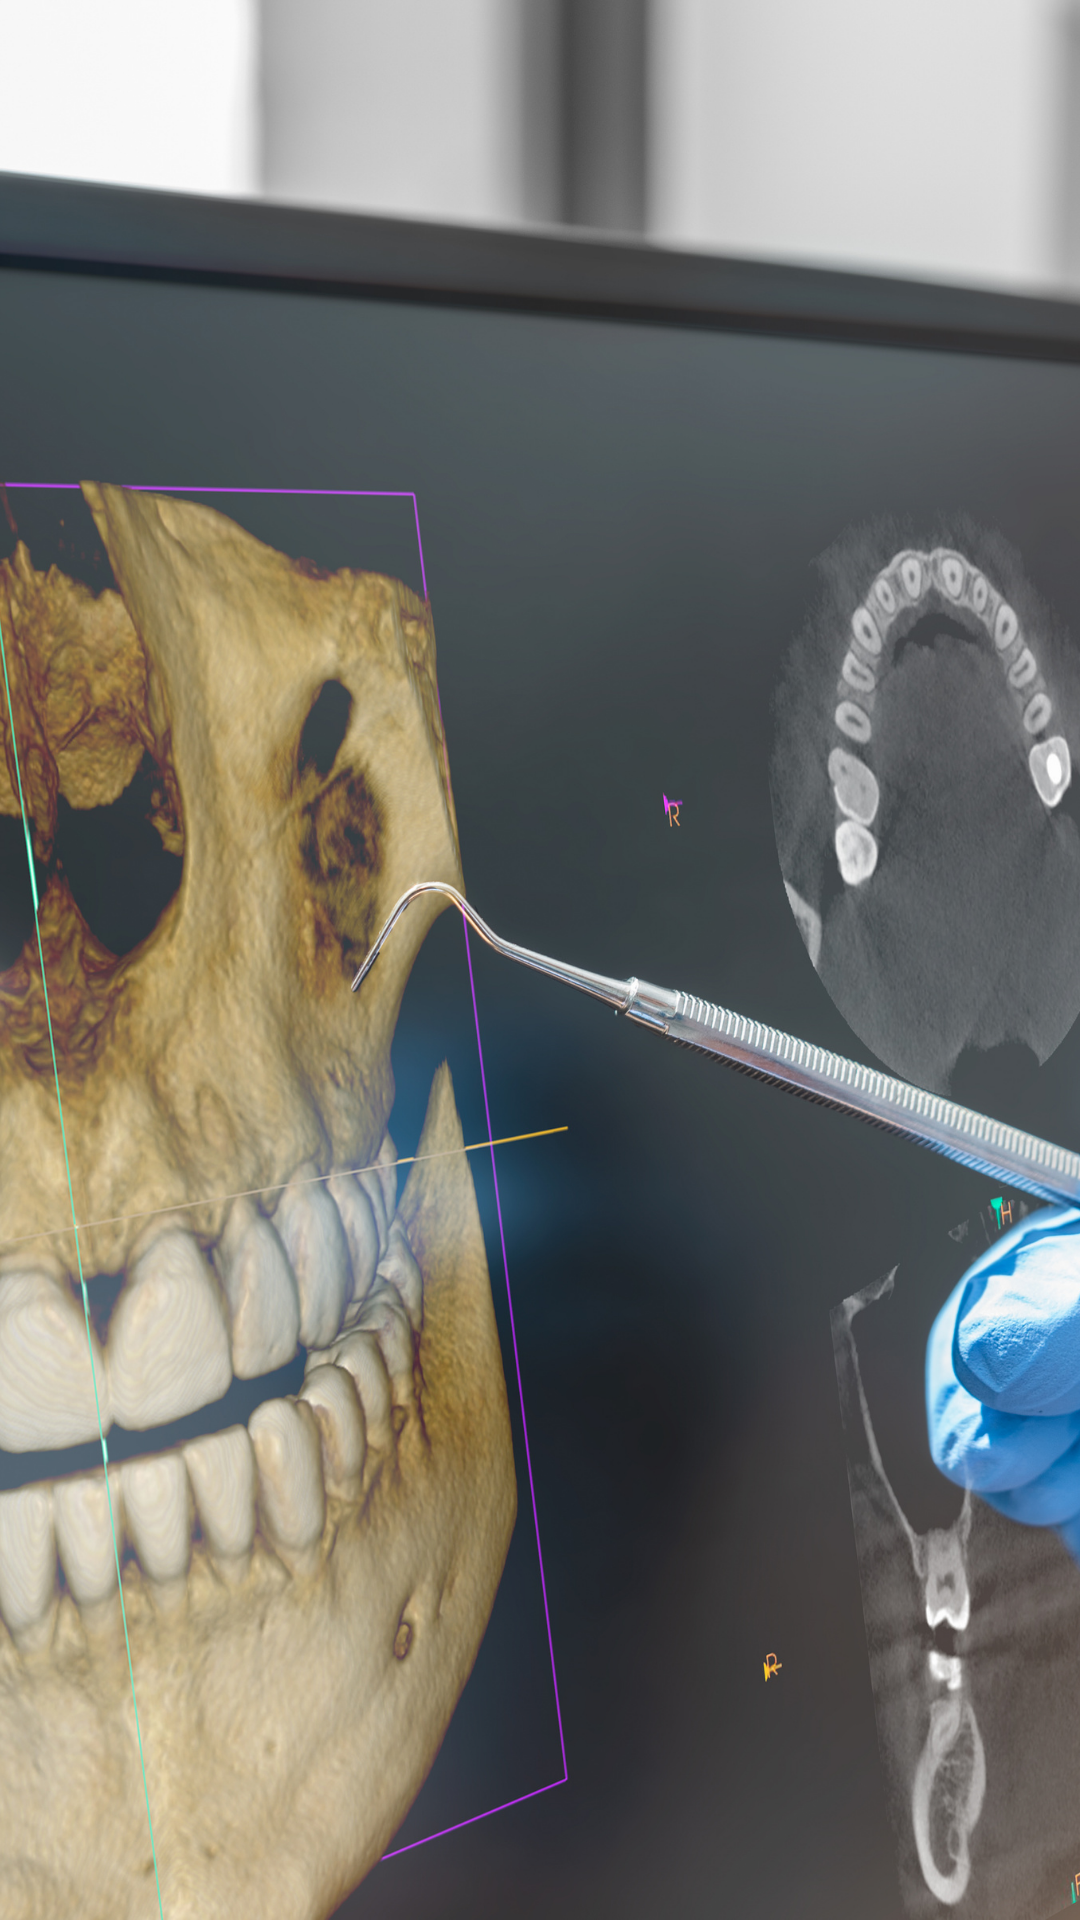

Equipos de última generación para diagnósticos de precisión milimétrica.

¿Necesitas imágenes tridimensionales precisas? Nuestras tomografías 3D te brindan diagnósticos milimétricos para planificación de tratamientos.

Un recorrido por nuestra tecnología, instalaciones y el equipo humano que hace la diferencia.